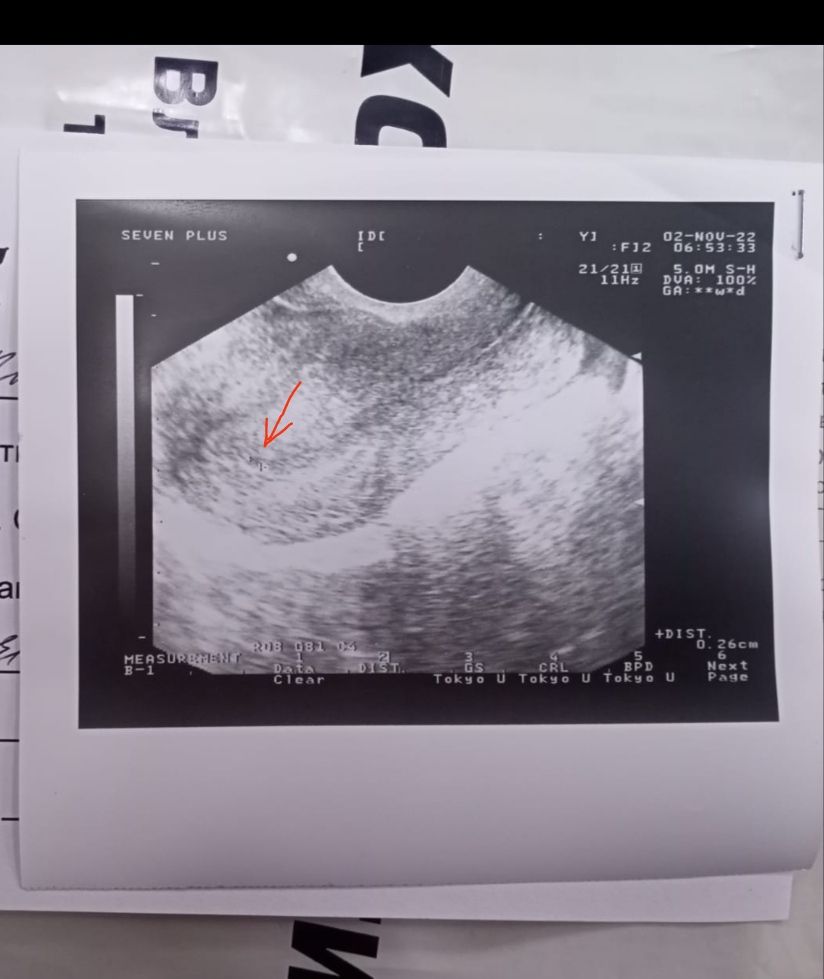

сегодня 29 сдавала опять хгч результат не пришел, на узи плодное яйцо 2 мм( врач сказал может быть и ложное)

врач странный, ккк такое мог сказать... если увидел плодное яйцо в матке, то как ложное, да и не мог он увидеть его при хгч 113

Эльси, почему не мог увидеть? Моя подруга пошла на УЗИ с сильными болями в низу живота за день до месячных, нашли яйцо 2 мм. Поставили срок 2-3 недели. За день до задержки там далеко не 1000 был ХГЧ.

Эльси, за неделю 1000? Я думаю врят ли. Если врач хороший и аппарат хороший, то найдёт. Я сама удивилась. По УЗИ вы же видите срок 2-3 недели. Явно не 1000 ХГЧ.Ткст на овуляцию был яркий на 13 день цикла. Она мне его скидывала, спрашивала овуляция или нет. Там прям ярчайшие полоски были, на 15 уже был отрец.

Da Ri, ну да, как то не очень динамика. Тут только наблюдать и ждать. Может быть цикл сбился и овуляция была позже и у вас еще просто маленький срок. Может быть бхб, это когда мало растет хгч, потом отсианавливается и начинаются месячные. Надо ждать результата хгч. Если прирост не очень , пересдавать и наблюдать за собой. Если внематочная, то появятся выделения, боли. На узи слишком рано бегать. При хгч 113 конечно ничего не увидят. После 1000 только вам могут точно плодное яйцо определить, до этого любую точку можно под вопросом как плодное яйцо россматривать. Поэтому не паникуйте, но держите руку на пульсе - сдавайте дальше хгч через день. Желаю вам благополучной беременности!